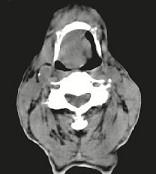

问题 男,74岁,咽喉部不适一年余,近两三个月咽喉疼痛,吞咽困难,CT如图所示,最可能诊断是()

选项 A.喉癌 B.会厌癌 C.声带癌 D.声门下区癌 E.跨声门型癌

答案 B